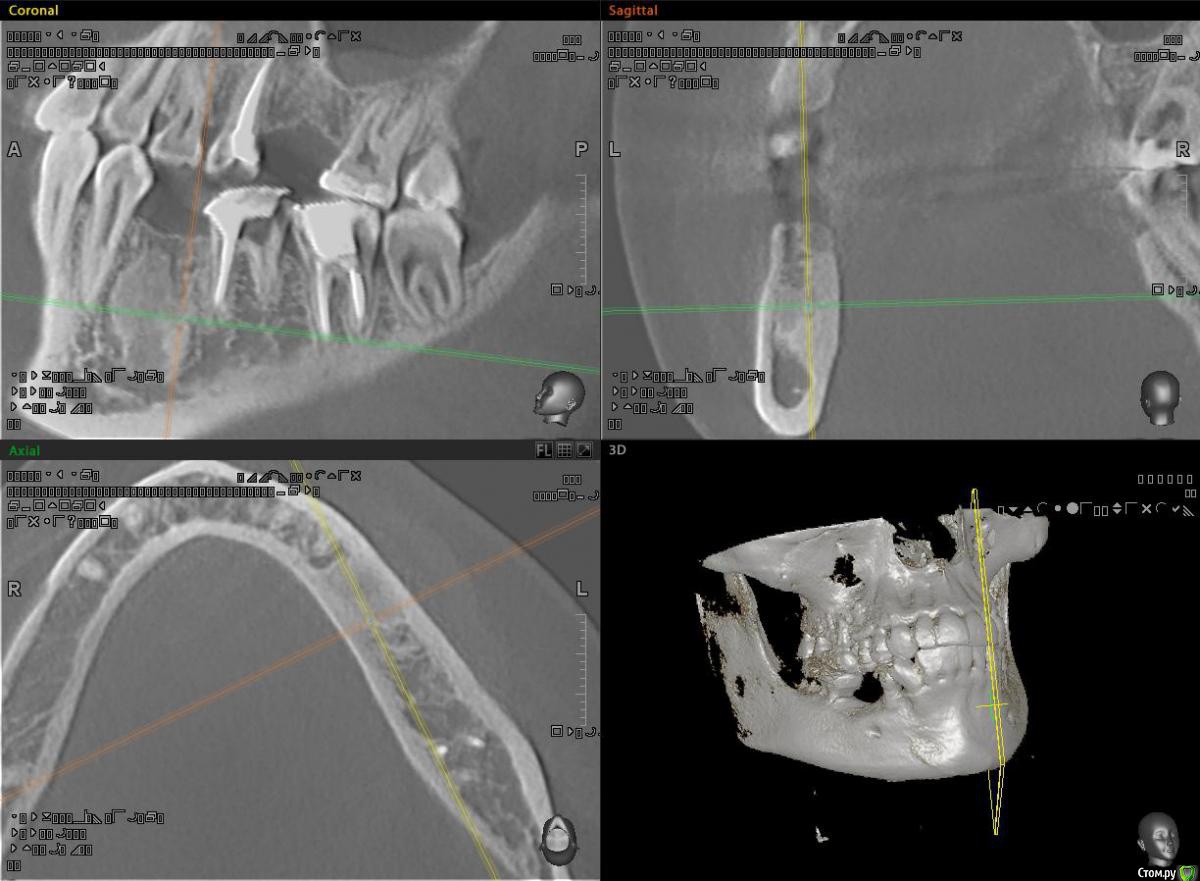

alekszander Опубликовано 16 декабря, 2015 Поделиться Опубликовано 16 декабря, 2015 Почитал тему про цементомы и посмотрел, чтов зависиости от года тактика менялась))Направлен пациент на возможность имплантации в области зуба ... ну назовем его 3.6.На Кт вот такой рисунок кости. Как понимаю, максимум что там было - молочный зуб,т.к. 4.6-4.8 на месте.1. Есть ли смысл туда сверлиться?2. Есть ли смысл отправить на гистологию,если не будем сверлиться и ортопед поставит мост?3. Главный вопрос Что это? Цементома? Ссылка на комментарий

bullbull Опубликовано 17 декабря, 2015 Поделиться Опубликовано 17 декабря, 2015 Что-то подобное обсуждалось пару недель назад. Ставьте. Оборотов поменьше - и вперёд. Ссылка на комментарий

red_butler Опубликовано 17 декабря, 2015 Поделиться Опубликовано 17 декабря, 2015 сюда просится астра с одноразовыми фрезами и по полному протоколу. Ссылка на комментарий

alekszander Опубликовано 5 февраля, 2016 Автор Поделиться Опубликовано 5 февраля, 2016 Пришло заключение из лаборатории: материал представлен мелкими кальцинатами без клеточных структур. Я как понимаю это по типу остеосклероза? 1 Ссылка на комментарий

alekszander Опубликовано 5 февраля, 2016 Автор Поделиться Опубликовано 5 февраля, 2016 Агаспасибо, будем имплантироваться. Ссылка на комментарий